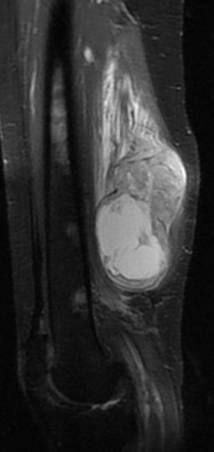

Synovialosarcome. Noter l’aspect hétérogène en T1, T2 et après injection de gadolinium